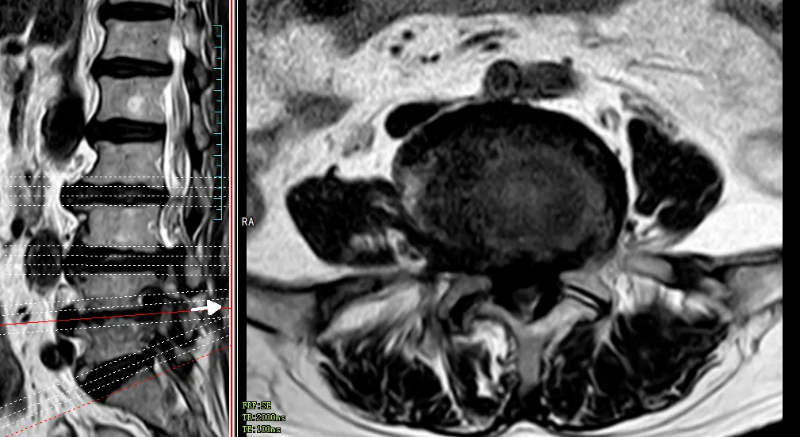

今年6月份,68歲的魯婆婆(化名)因反復腰痛伴雙下肢麻木5年,加重伴右下肢乏力1個月后,到我院康復醫學科住院治療,在藥物治療、康復理療等治療效果欠佳的情況下,來到脊柱外科會診。姚仕奮主任醫師仔細查看魯婆婆的情況及其磁共振片子后發現,胸10、胸12、腰1椎體骨質疏松性壓縮骨折,導致魯婆婆胸腰背部疼痛明顯,因胸椎黃韌帶骨化并椎管狹窄致雙下肢疼痛、麻木、乏力,右下肢肌力下降,雙下肢肌張力增高,右下肢膝腱反射亢進,雙側巴氏征陽性,導致魯婆婆無法行走。

文章配圖

△磁共振提示胸10、胸12、腰1椎體壓縮性骨折,胸9/10、胸10/11黃韌帶骨化、椎管嚴重狹窄。